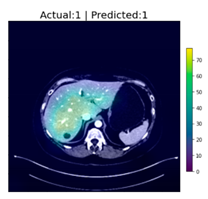

| Image Number | Overlaid Image | Deep Lesion Label | CNN Result | Clinical Radiologist’s Diagnosis | Grad-CAM Helpfulness |

|---|---|---|---|---|---|

| 1 | ![]() | Has Tumor | Has Tumor | Has Tumor | Some |

| 2 | ![]() | Has Tumor | Has Tumor | Has Tumor | Yes |

| 3 | ![]() | Has Tumor | Has Tumor | Has Tumor | Yes |

| 4 | ![]() | Has Tumor | Has Tumor | Has Tumor | Yes |

| 5 | ![]() | Has Tumor | Has Tumor | Has Tumor | Yes |

| 6 | ![]() | No Tumor | Has Tumor | Has Tumor | Yes |

| 7 | ![]() | Has Tumor | Has Tumor | Has Tumor | Yes |

| 8 | ![]() | Has Tumor | Has Tumor | Has Tumor | Yes |

| 9 | ![]() | Has Tumor | Has Tumor | Has Tumor | Some |

| 10 | ![]() | Has Tumor | Has Tumor | Has Tumor | Yes |

| 11 | ![]() | Has Tumor | Has Tumor | No Tumor (Cyst) | Some |

| 12 | ![]() | Has Tumor | Has Tumor | Has Tumor | Yes |

| 13 | ![]() | Has Tumor | Has Tumor | No Tumor | Yes |

| 14 | ![]() | Has Tumor | Has Tumor | No Tumor (Inflammation of the Biliary Tract) | Some |

| 15 | ![]() | No Tumor | Has Tumor | No Tumor (Cyst) | Some |

| 16 | ![]() | Has Tumor | Has Tumor | Has Tumor | Yes |